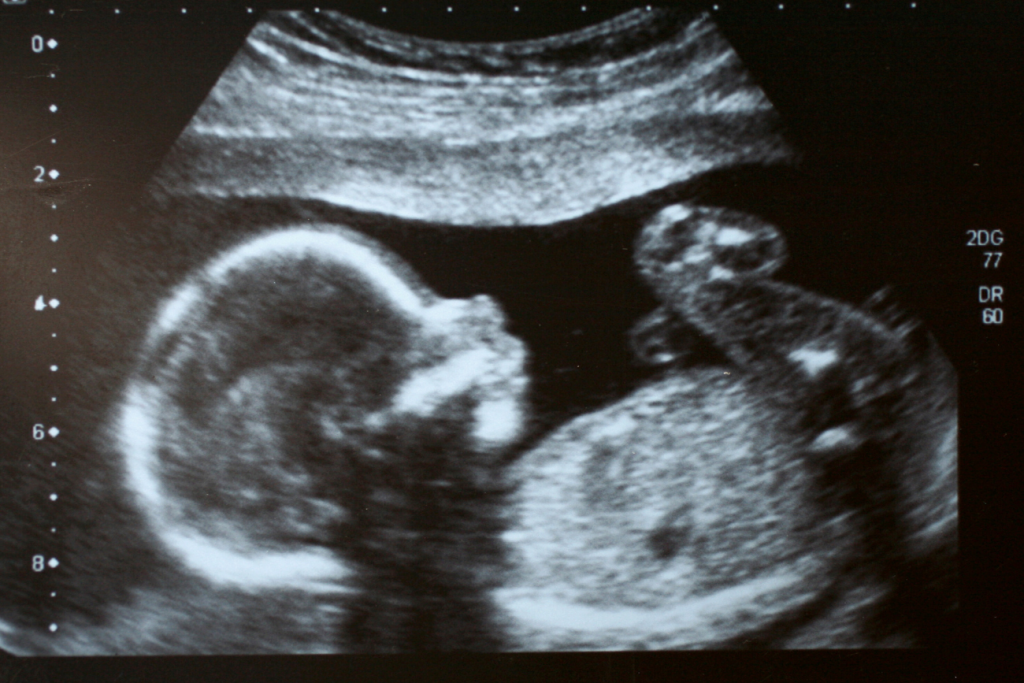

Estas técnicas de diagnóstico prenatal involucran diferentes tipos de ecografías especializadas y se seleccionan según las necesidades específicas de cada paciente y la indicación clínica. El objetivo es proporcionar una evaluación completa y precisa del feto para orientar el manejo prenatal y preparar a los padres para el nacimiento de su hijo.

En los años noventa, se describió como el exceso de piel de los individuos con síndrome de Down podía visualizarse mediante una ecografía como un aumento de la translucencia nucal (líquido observado a nivel del cuello fetal) en el tercer mes de vida intrauterina. La medición de la translucencia nucal durante la ecografía del primer trimestre proporciona información valiosa sobre el desarrollo del feto.

Un aumento en la translucencia nucal puede indicar la presencia de ciertas anomalías cromosómicas, como el síndrome de Down. Esta detección precoz permite a los médicos y padres iniciar investigaciones adicionales para confirmar el diagnóstico y considerar opciones de manejo prenatal.